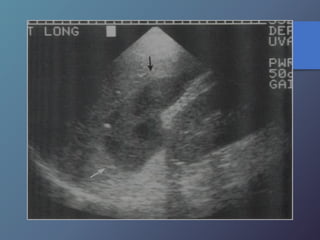

Abscesos Hepáticos

Parasitarios Hidatidosis

• Infestación por echinococcus granulosus.

• Ecográficamente son redondas u ovales, anecogénicas.

• Pared de 1mm de grosor que puede calcificarse.

• Se presentan como:

• Quistes simples sin arquitectura interna.

• Quistes con endoquistes desprendidos.

• Quistes con quistes hijos en su interior.

• Masas muy calcificadas.

Abscesos Hepáticos Parasitarios Hidatidosis •Infestación por echinococcus granulosus. • Ecográficamente son redondas u ovales, anecogénicas. • Pared de 1mm de grosor que puede calcificarse. • Se presentan como: • Quistes simples sin arquitectura interna. • Quistes con endoquistes desprendidos. • Quistes con quistes hijos en su interior. • Masas muy calcificadas.